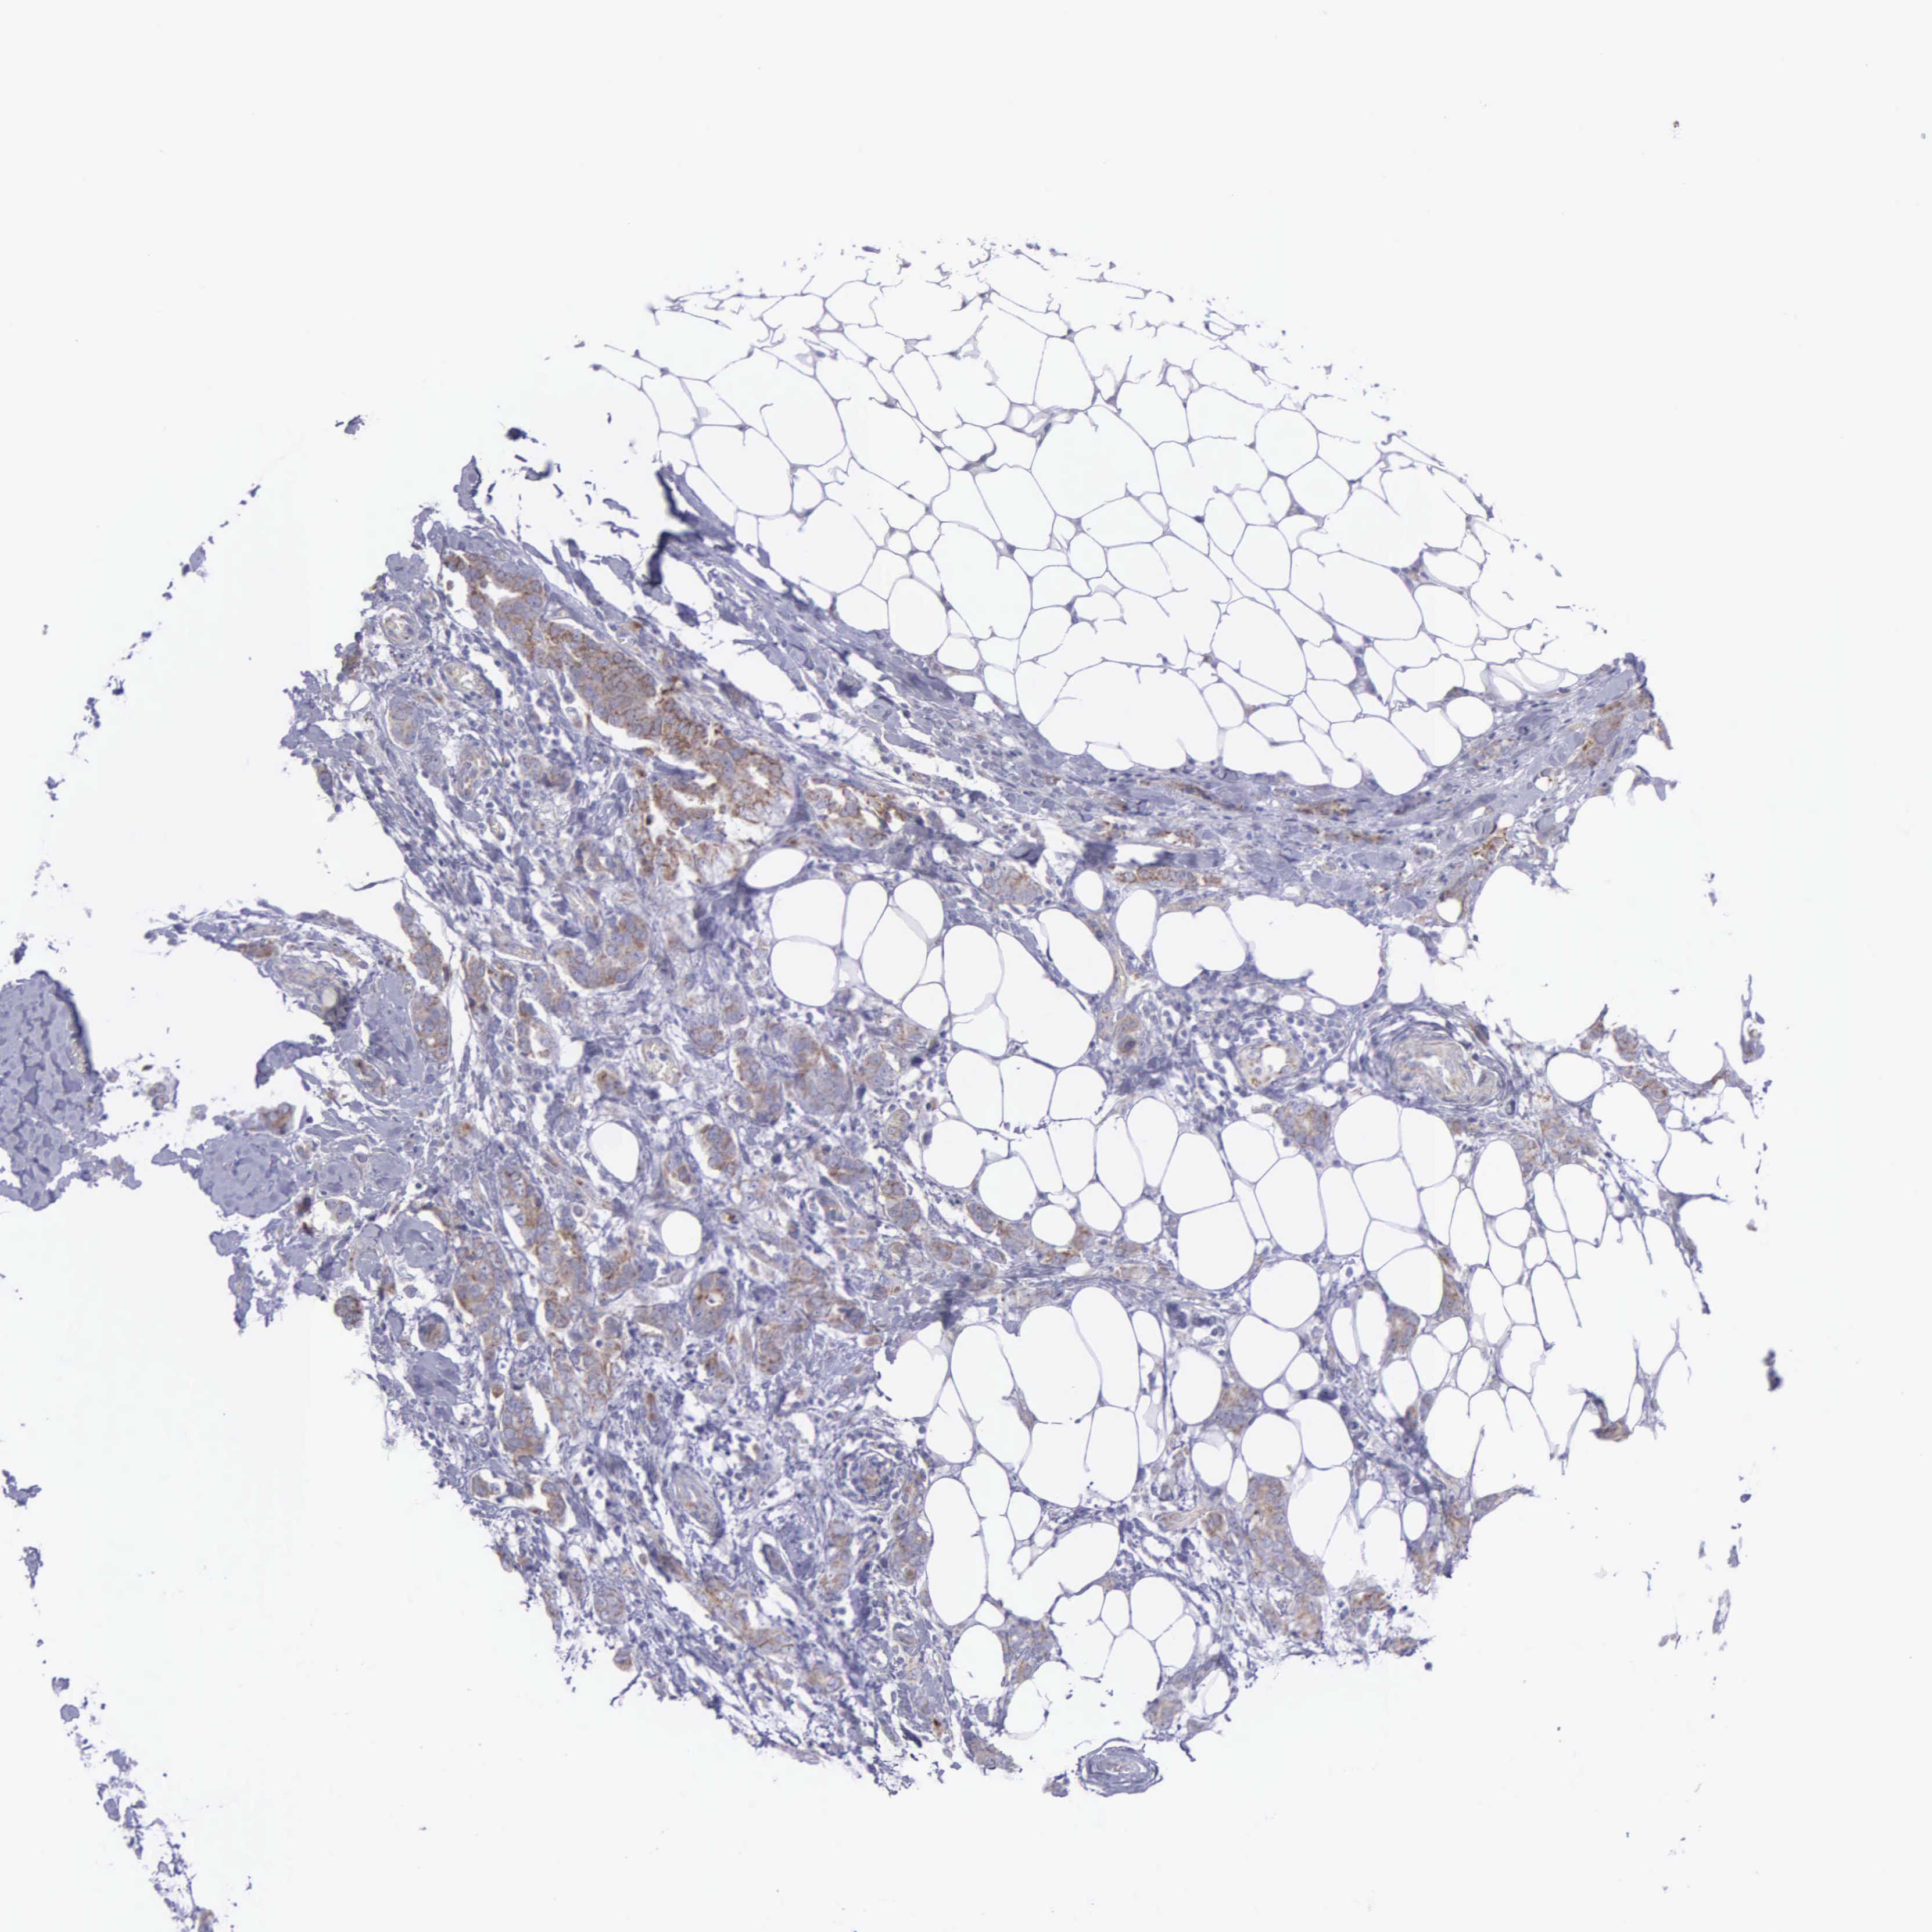

CANCER BREAST CANCER Show tissue menu

BRCA TCGA BRCA VALIDATION PROTEIN EXPRESSION